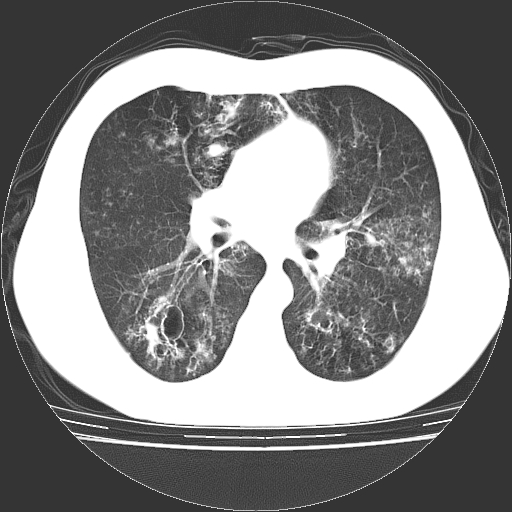

以下是引用zyx168在2006-12-4 15:30:00的发言:[br]经典!支气管肺囊肿并感染。

以下是引用dyqct在2006-12-4 17:11:00的发言:[br]典型的囊状支扩合并感染。

以下是引用liaoqiang在2006-12-4 16:12:00的发言:[br]局部肺叶内可见扩张的支气管壁,考虑为支扩。部份囊样影内有小液平和肺内散布斑片征影、小结节及纤维灶,提示支扩伴感染,且由于局部呈现有树芽征感染以结核可能性大。

以下是引用zhoucan076在2006-12-4 16:48:00的发言:[br]囊状支扩合并感染